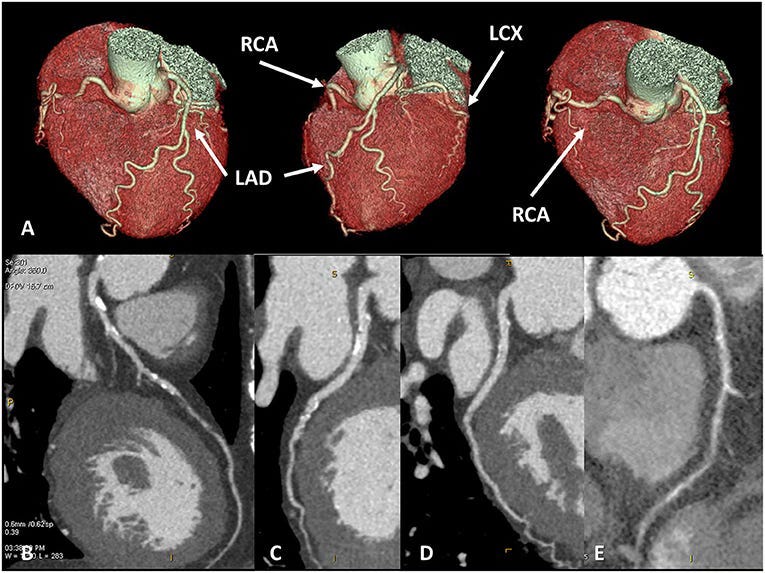

CT Coronary Angiogram (CTCA)

The second type of cardiac CT is a CT coronary angiogram which involves slightly more radiation and also some contrast.

This scan gives a lot more anatomical detail and also assesses for non-calcified plaque.

If this scan is normal, then you do not have any calcified or non-calcified plaque, and by extension, your near-term risk of a heart attack is very low.

“If there ain’t no plaque, there ain’t no heart attack”.

When used to assess those presenting with chest pain, the use of CTCA led to a 41% reduction in the risk of future major heart events, including heart attacks and death from coronary artery disease2.